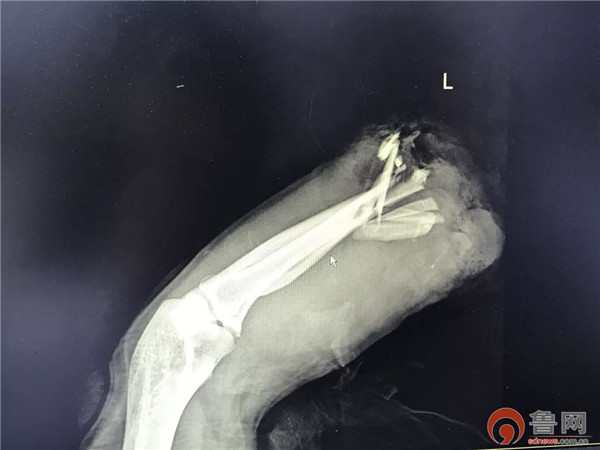

术前X光片

1月9日下午,郭先生在工作时被冲压机压伤了左前臂,致左前臂中段完全离断。发生事故后,家属将他送到了青岛明亮手足外科医院,一般断臂再植有“黄金6小时“的抢救时间之说,超过6小时后断离的手臂血管坏死机率大增而会错过最佳手术时间,因此,该院手外科专家林彬院长和手外科主任薛亚军大夫必须尽快将郭先生断离手臂的血管缝合,才有机会让他保住手臂。

左前臂中段完全离断